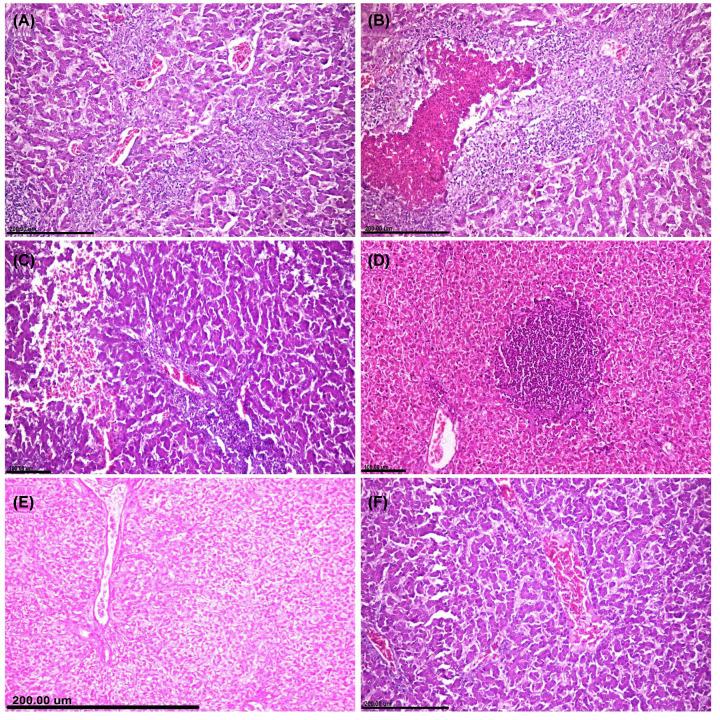

比较氧化铜、银和壳聚糖-银纳米粒子对肉鸡大肠杆菌感染的杀菌效果。

Comparative assessment of the bactericidal effect of nanoparticles of copper oxide, silver, and chitosan-silver against Escherichia coli infection in broilers.

Escherichia coli infection is considered one of the most economically important multi-systemic diseases in poultry farms. Several nanoparticles such as silver, chitosan, and copper oxide are known to be highly toxic to several microbes. However, there are no data concerning their success against in vivo experimental E. coli infection in broilers. Therefore, the present study was designed to investigate the bactericidal effect of low doses of CuO-NPs (5 mg/kg bwt), Ag-NPs (0.5 mg/kg bwt), and Ch-Ag NPs (0.5 mg/kg bwt) against E. coli experimental infection in broilers. One hundred chicks were divided into five groups as follows: (1) control; (2) E. coli (4 × 108 CFU/ml) challenged; (3) E. coli +CuO-NPs; (4) E. coli +Ag-NPs; (5) E. coli +Ch-Ag NPs. The challenged untreated group, not NPs treated groups, recorded the lowest weight gain as well as the highest bacterial count and lesion score in all examined organs. The highest liver content of silver was observed in Ag-NPs treated group compared with the Ch-Ag NPs treated group. Our results concluded that Ch-Ag NPs not only had the best antibacterial effects but also acted as a growth promoter in broilers without leaving any residues in edible organs. We recommend using Ch-Ag NPs in broiler farms instead of antibiotics or probiotics.

摘要